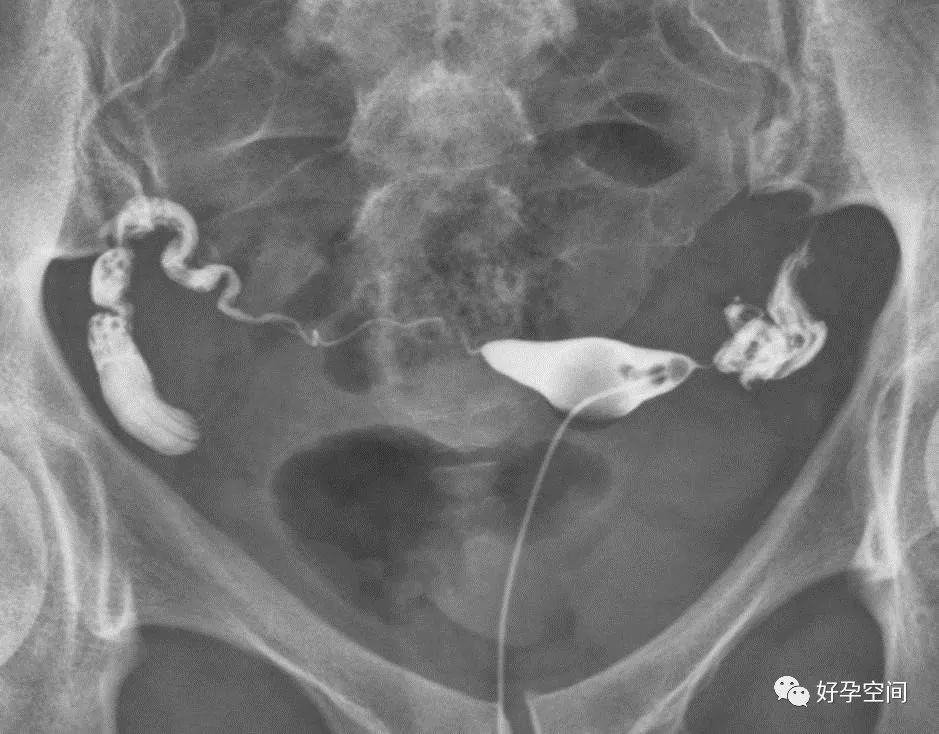

双侧输卵管反向走行(一侧上行,对侧下行)